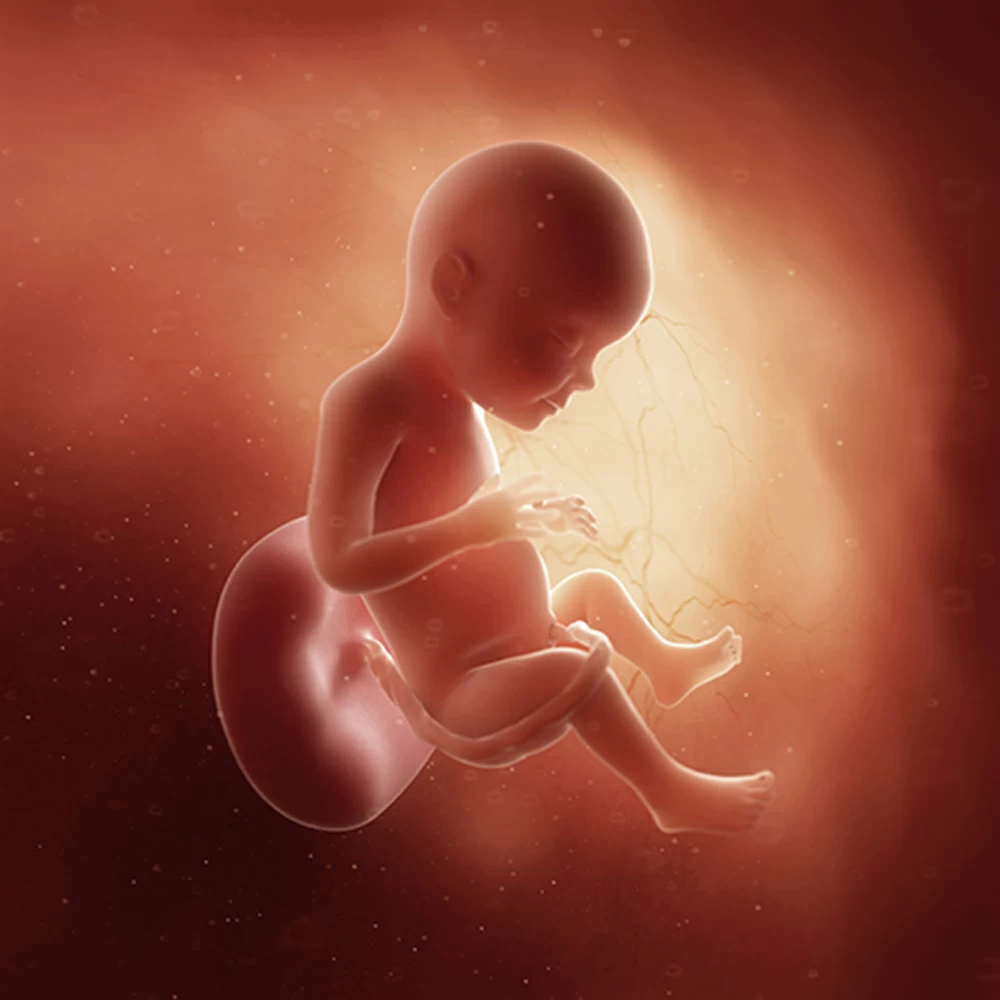

Неделя № 30

Масса тела увеличивается до 1300-1350 грамм, рост остается примерно тем же – около 38-39 см.

Постоянно накапливается подкожная жировая клетчатка, расправляются кожные складки. Ребенок приспосабливается к недостатку места и принимает определенное положение: сворачивается, руки и ноги скрещиваются.